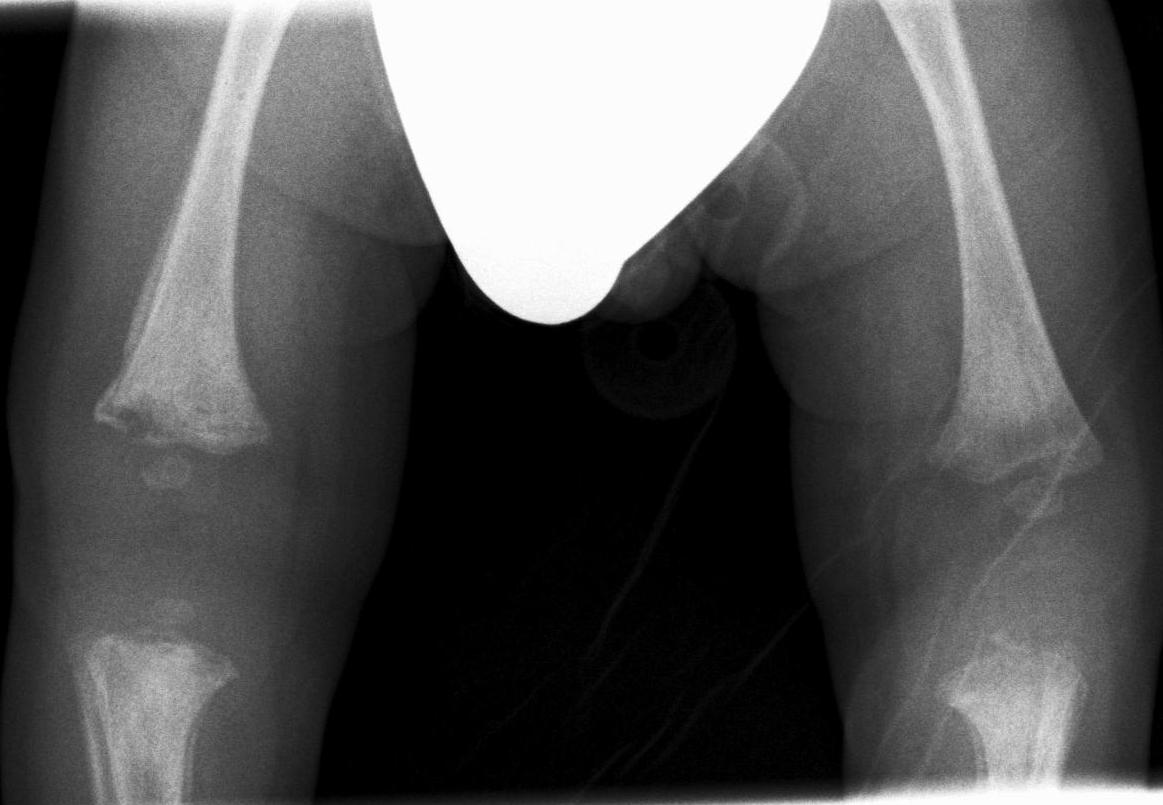

Image

43. Comparison Radiograph of the knees. On the distal-lateral epiphysis of the right femur “corner” fracture is seen, lytic area, periosteal reaction. Both proximal tibia, on the visible part of the picture show periosteal reaction. Battered child.